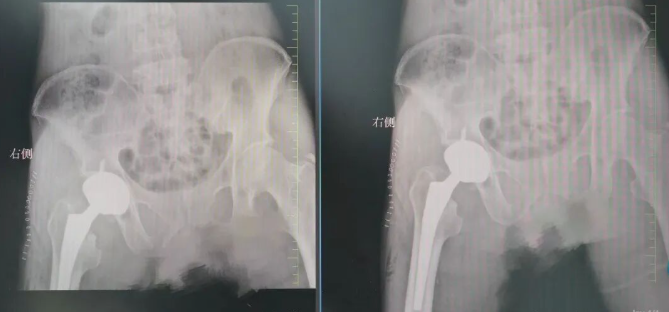

多方打听后,患者了解到长春国文医院在骨科疾病诊疗领域,尤其是股骨头坏死治疗方面,拥有深厚的专业实力与丰富的临床经验,遂满怀希望前来就诊。骨科门诊医生详细询问患者病史,仔细查看过往检查报告,并进行初步检查后,确诊患者为 “股骨头坏死”。考虑到患者病情反复且逐渐加重,保守治疗效果不佳,医生建议进行全髋关节置换手术。

考虑到患者已步入花甲之年,为在保障手术安全性的同时,最大程度契合患者术后康复需求,骨科医疗团队经综合评估后,制定了 “分期手术” 的个性化治疗方案。团队决定优先为患者实施右侧人工全髋关节置换术,以缓解其右侧剧烈疼痛,改善关节活动功能。待患者右侧髋关节功能恢复稳定后,医疗团队将再次对其左侧病灶情况进行全面评估。